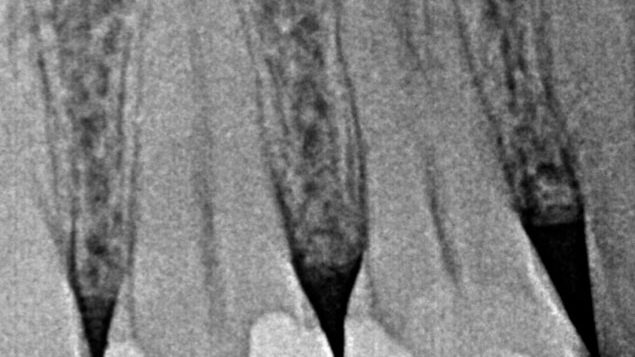

Necrosis pulpar en diente 45 con bifurcación en el tercio medio del conducto Caso clínico del doctor Francisco…